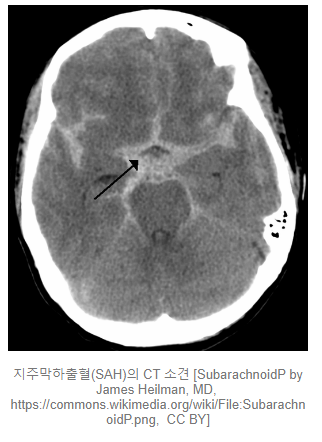

지주막하출혈(Subarachnoid hemorrhage)

지주막(Arachnoid mater)과 연뇌막(Pia mater) 사이에 발생. CT에서 별 모양으로 관찰됩니다. 머리의 외상 환자에서 뇌출혈 중 가장 흔하게 발견됩니다. 외상 없이도 자발적으로 발생할 수 있습니다.

양이 적을 경우에는 두통 등의 주증상이며, 양이 늘어날 경우에는 각종 신경학적 증상이 발생할 수 있으며, 가장 심할 경우에는 의식이 소실되어 혼수 상태에 빠질 수 있습니다.

치료는 이전 포스팅(아래 링크)를 참조하여주시길 부탁드립니다.